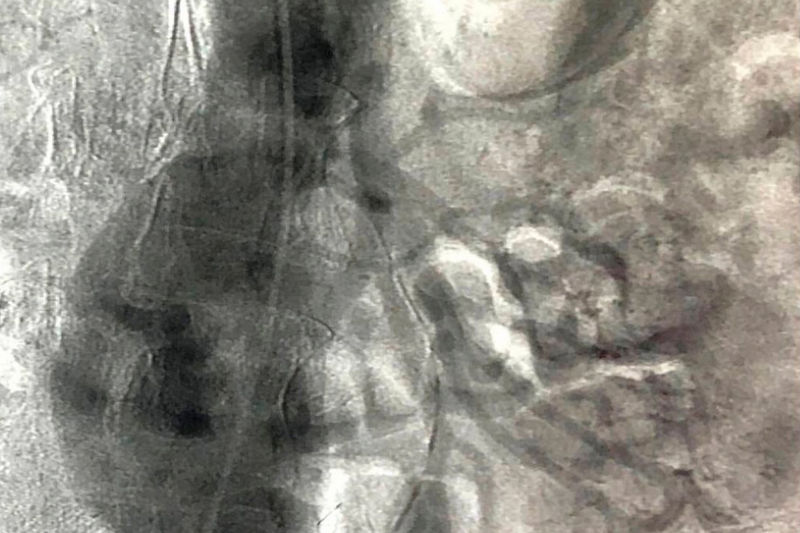

Фото аневризмы брюшной аорты предоставлено комитетом здравоохранения Волгоградской области

Сердечно-сосудистые хирурги Волгоградской областной клинической больницы №1 провели сложнейшую операцию: серез небольшие разрезы на бедрах врачи установили внутри аневризмы стент-графт. Это искусственный сосуд из металлической сетки, которая особой конструкции, которая внутри покрыта герметичной полимерной тканью. Сетка фиксирует устройство к стенкам аорты и подвздошных артерий, а полимерная ткань изолирует просвет сосуда от полости аневризмы. В результате кровь перестает попадать в аневризматический мешок, и риск дальнейшего роста и разрыва аневризмы значительно уменьшается. ⠀